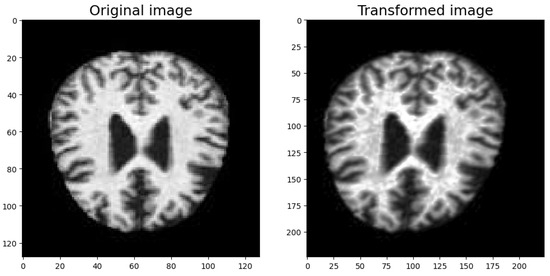

Figure 3 shows a sample of an original image from the dataset over which transformation was applied. The image to the right is the result of the full augmentation sequence. Although the transformation modifies the view of images significantly, it does not lose the characteristics that are used in AD classification.

Figure 3. Original vs. transformed image after full augmentation sequence.

Mathematics 13 01927 g003